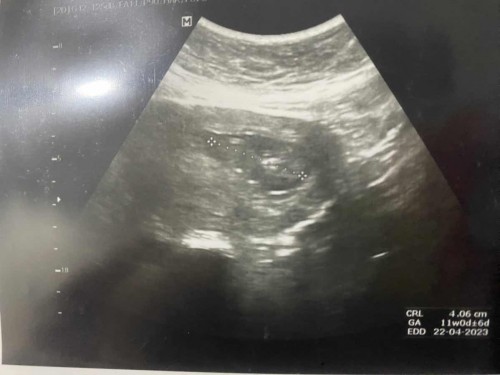

ซาวน์ครั้งที่2#ขอบคุณสำหรับคำตอบค่ะ